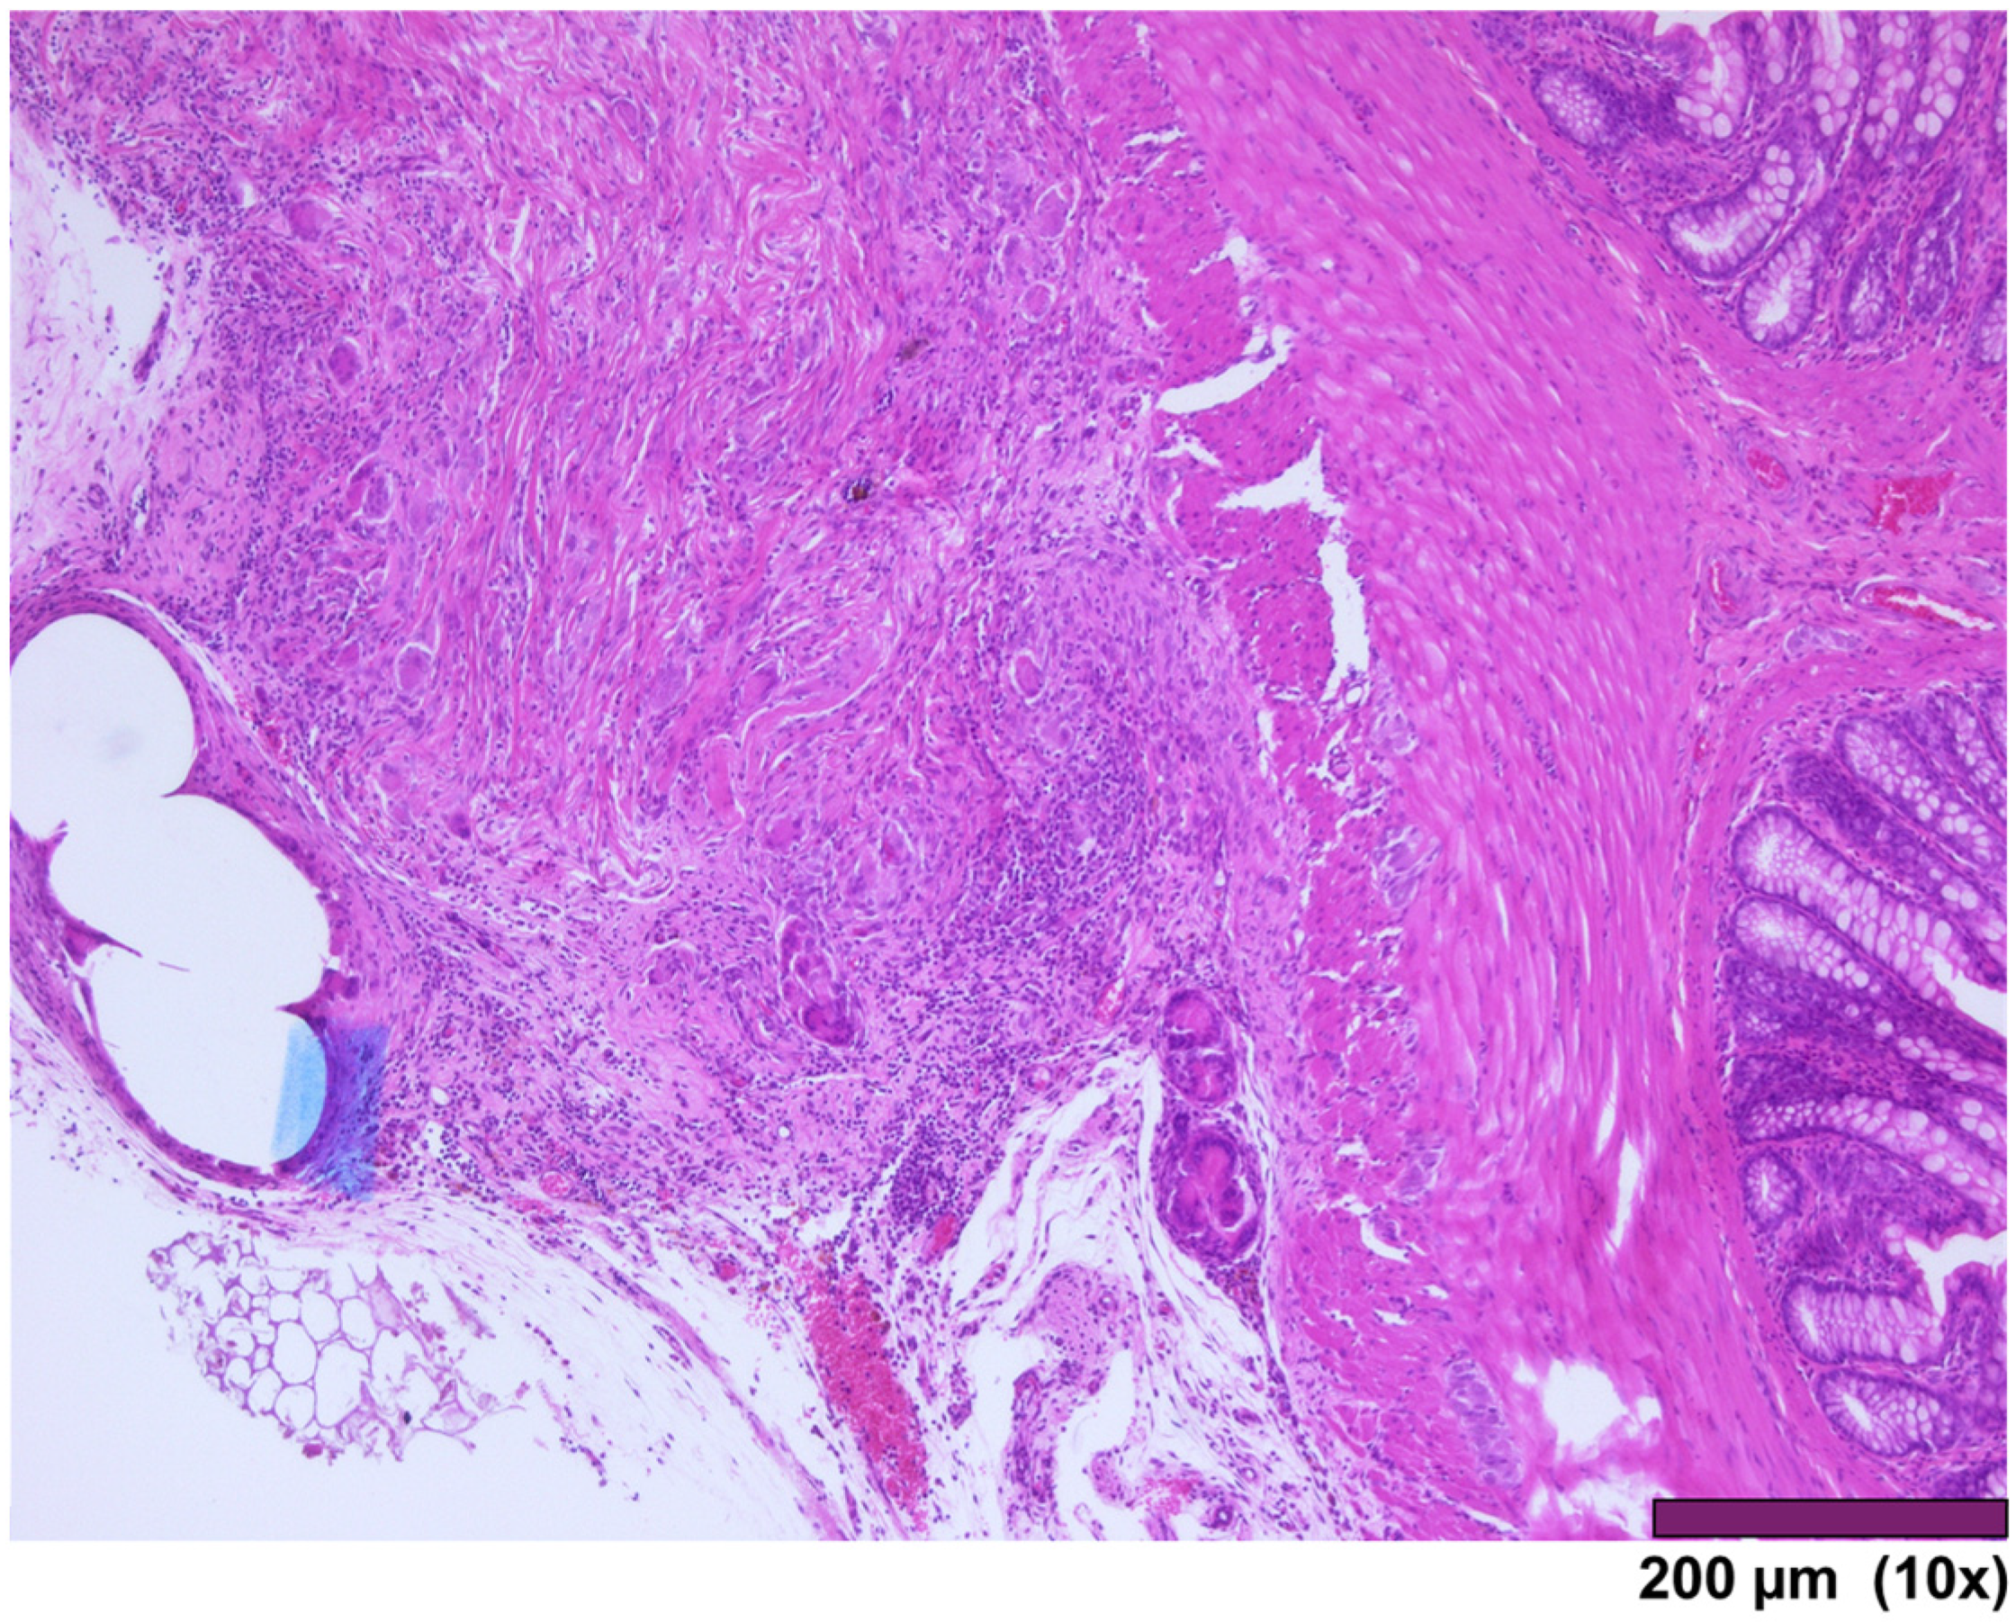

The small intestine wall regenerated with fibrosis and with different degrees of mononuclear inflammatory cell infiltrations. Neovascularization could be seen as well (Figure 7). In three cases, ulceration of the mucosa was observed, where the muscularis propria was replaced by granulation tissue and inflammatory cells (Figure 8).

Figure 7. Small intestinal wall covered by granulation tissue and early fibrosis, both with neovascularization and infiltration of inflammatory cells (10×, HE).